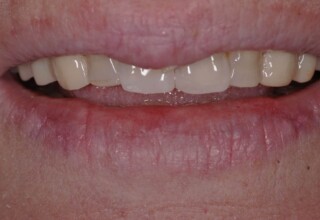

Οι όψεις πορσελάνης είναι ο καλύτερος τρόπος αντιμετώπισης αισθητικών προβλημάτων στην πρόσθια περιοχή του στόματος. Συνδυάζουν συντηρητική αφαίρεση οδοντικής ουσίας και πολύ υψηλή αισθητική απόδοση. Στο παρακάτω εκτεταμένο περιστατικό υπήρχαν: παλαιά σφραγίσματα, δυσχρωμίες, κακό σχήμα και μήκος δοντιών, κακή αναλογία δοντιών-ούλων. Έγινε προσεκτικός εργαστηριακός σχεδιασμός σε εκμαγεία απ’όπου προέκυψαν προσωρινές όψεις που τοποθετήθηκαν στο στόμα για δοκιμή και διορθώσεις. Όταν οριστικοποιήθηκαν οι μετατροπές, οι προσωρινές χρησιμοποιήθηκαν σαν οδηγός για τις μόνιμες. Οι πέντε μόνιμες όψεις πορσελάνης που κατασκευάστηκαν για τα πέντε πρόσθια δόντια της άνω απεκατέστησαν σχεδόν άψογα την αισθητική εμφάνιση της ασθενούς.